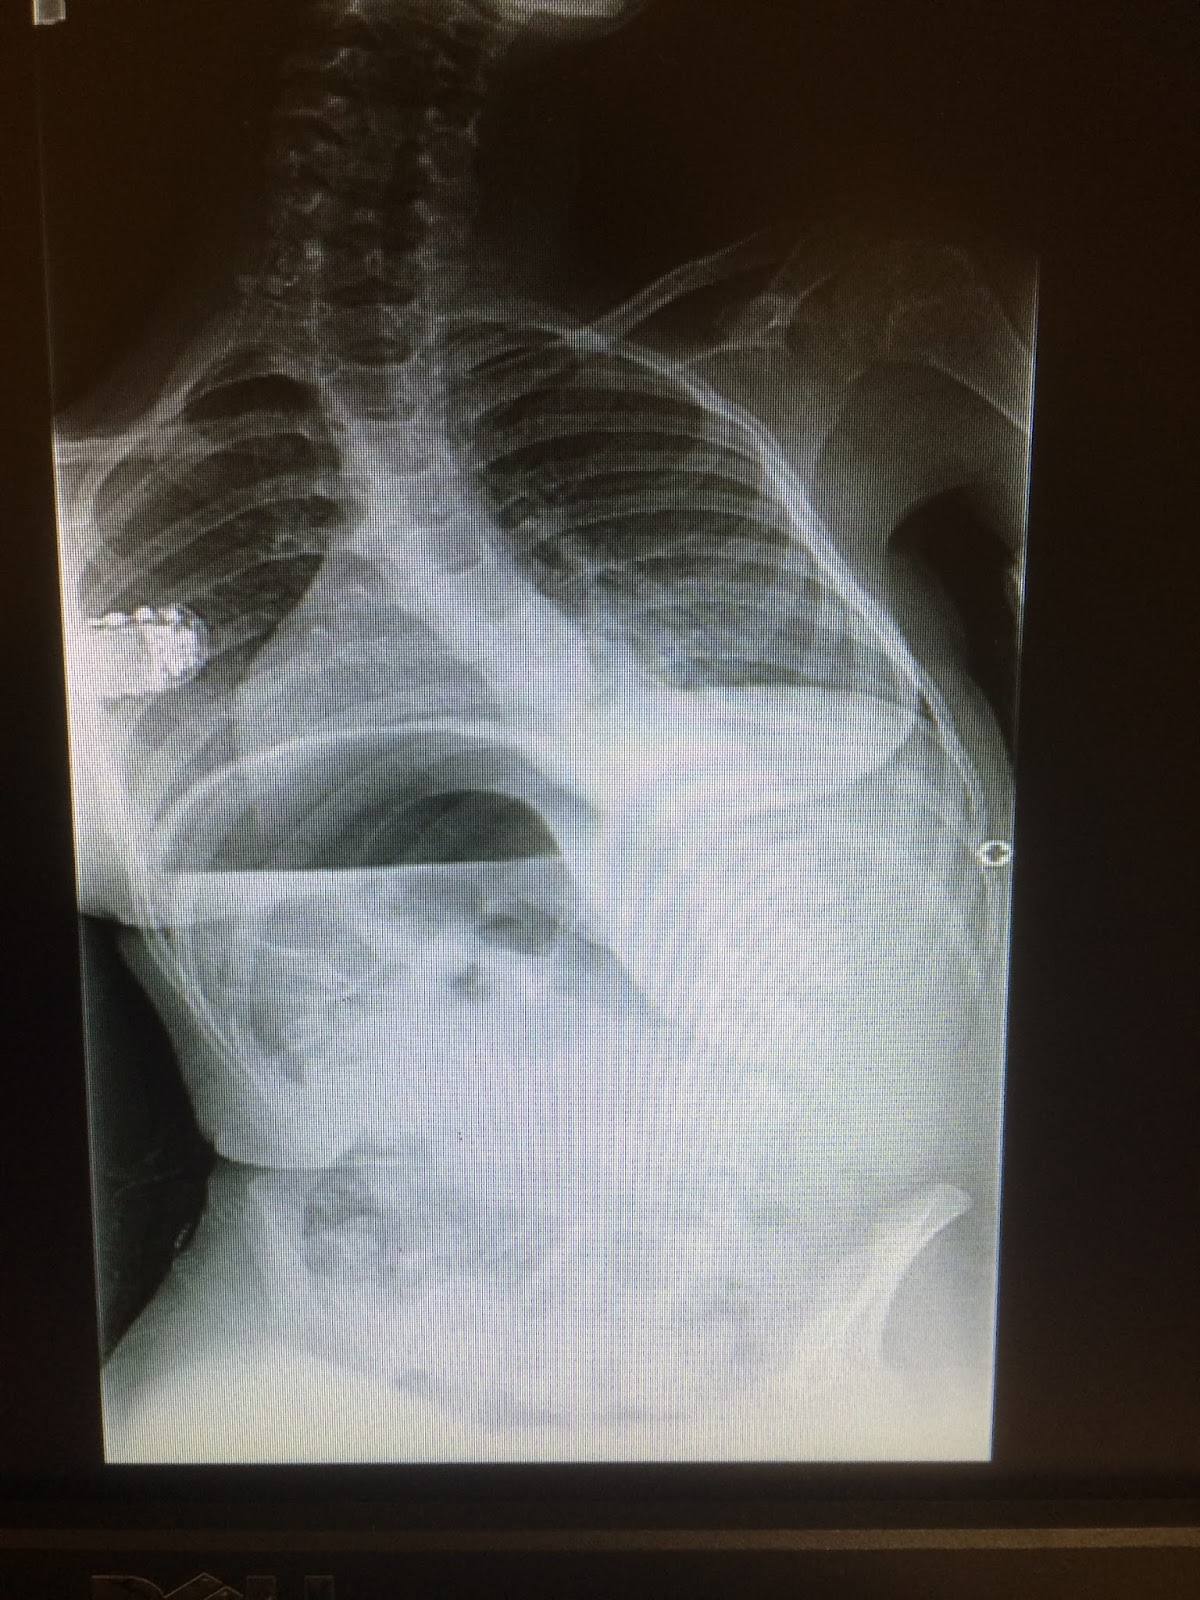

Then it was like I don’t know 11 AM and we were in a room with Dr. White where he was excited to show us her before and after X Ray, surgery was successful!

![]() |

| pre surgery 70 degree curve |

Her pre surgery curve was 70 degrees sitting. She went from a 50 to a 70 in a short amount of time and was only getting worse. Surgery wasn’t a cosmetic or really optional choice, she needed to be straightened to have a healthy body. She is now very straight.